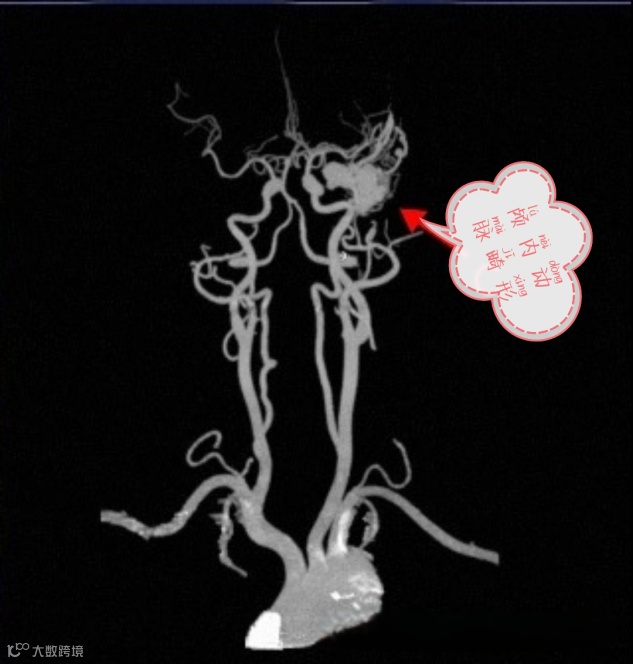

头颈部CTA即头颈部CT血管成像,是经静脉注入含碘造影剂后,经过CT机扫描,通过不同组织对X线的吸收差异,形成不同灰度的图像,再经过后处理软件去除骨及软组织,形成血管三维重建图像。具有快速、无创、并发症少、特异性和敏感性高等特点。

头颈部CTA能够显示脑血管的主干及较大分支,对脑血管疾病起到筛选和初步诊断作用,同时还能显示病变血管周围脑组织的病理性改变。

我们不仅仅是在血管疾病发生后,才需要做头颈部CTA,如果已经发生出血、脑梗死等,预后也会一定程度影响生活质量。所以将头颈部CTA作为常规体检项目,可以提前了解颅内是否有动脉瘤、血管狭窄程度等情况,达到“防大于治”的效果。